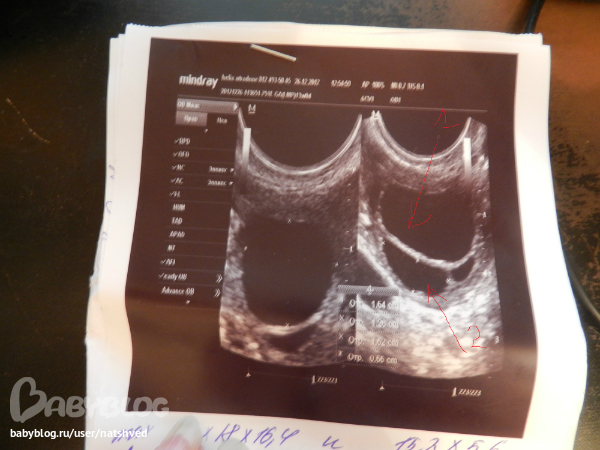

2 дня назад было 2ДФ

14,7*12,3 и 12,8*7,8

сегодня соответственно

16,4*12,4*18 и 15,2*6,6

Второй что то какой то узкий